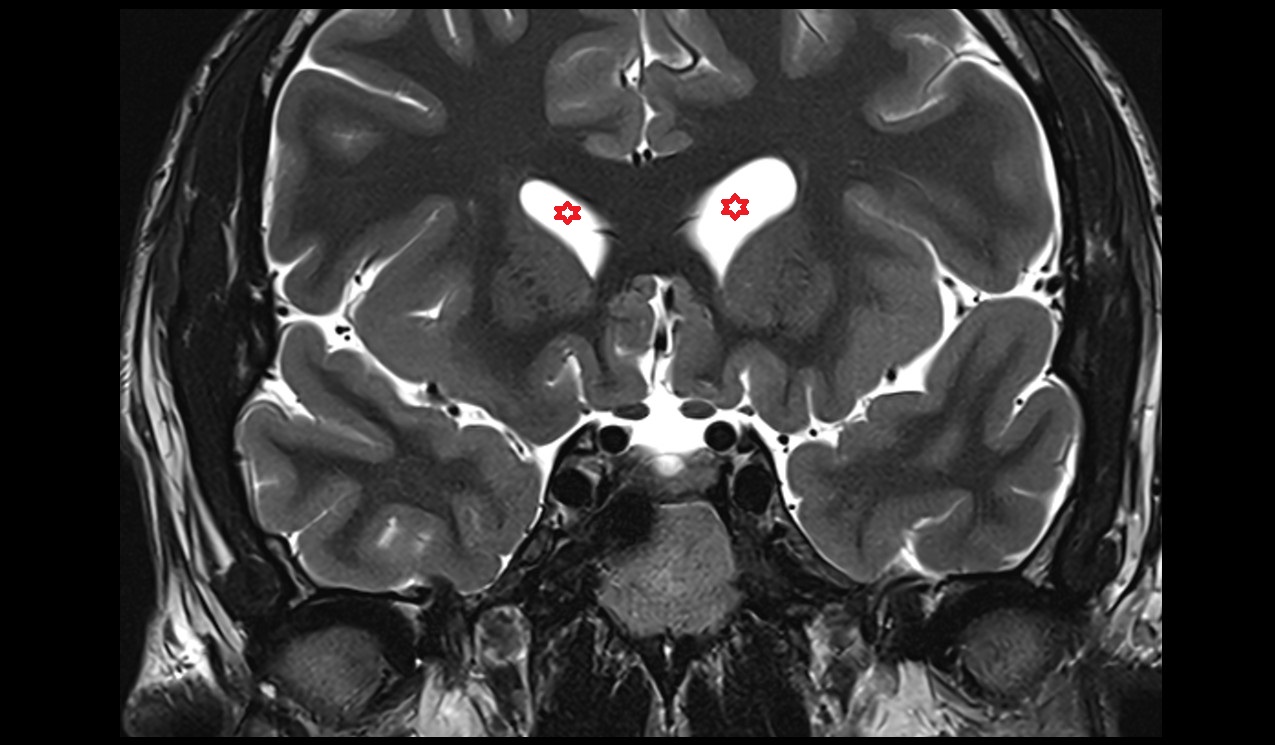

- Central part of lateral ventricle

- Frontal horn of lateral ventricle

- Temporal horn of lateral ventricle

- Third ventricle